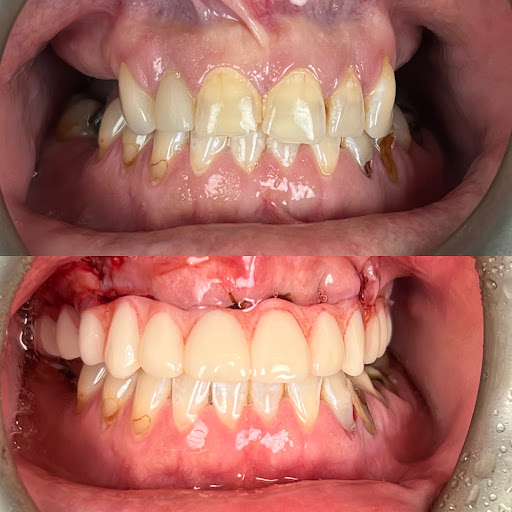

Signature Smiles Family Dentistry

Photos